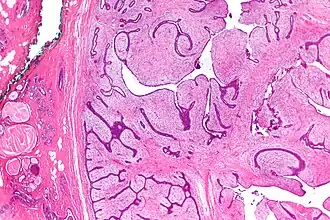

![]() Micrografía de un cistosarcoma filoides (a la derecha de la imagen). | ||

El cistosarcoma o tumor filoides es un tumor predominantemente benigno y raro que ocurre casi exclusivamente en el seno femenino. Su nombre deriva de las palabras griegas sarcoma que es un tumor carnoso y filo que significa hoja. El tumor tiene la apariencia de un gran sarcoma maligno, toma la característica forma de hoja cuando está seccionado y exhibe espacios epiteliales quísticos cuando se ve histológicamente. Debido a que son tumores benignos, el nombre de sarcoma no se emplea con mucha frecuencia, teniéndose preferencia por la terminología tumor filoides.[1]

El tumor filoides es el neoplasia no-epitelial más frecuente en las mamas, pero representa solo un 1% de todos los tumores de la mama. Es un tumor de crecimiento rápido, bajo el microscopio puede ser un tumor de pocos centímetros o bien puede presentar lesiones masivas de hasta 30 cm.[1] El aspecto es carnoso, blanco o grisáceo y firme, lobulado con hendiduras quísticas y áreas de necrosis y hemorragia. Tiene cierto parecido histológico al fibroadenoma, pero luce con mayor celularidad, el epitelio es benigno con un estroma que rodea al epitelio de características atípicas e hipercelular.[2]